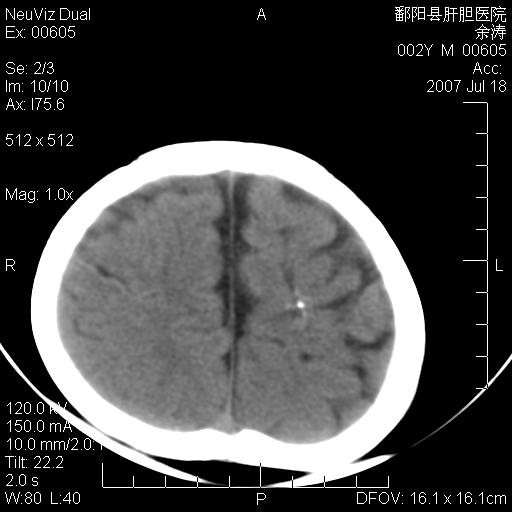

男性 2岁:平时智力障碍。外伤后行颅脑平扫。

左颞叶“萎缩”,可见不规则高密度影,并左侧室扩大,呈负占位效应...支持考虑先天发育异常(血管发育畸形)可能性大,建议结合进一步检查了解。

左颞叶“萎缩”其内可见不规则点条状高密度影,并左侧室扩大,考虑颅面血管瘤病

脑裂畸形;左侧脑脑萎缩;透明隔囊肿;血管畸形?

开唇型脑裂畸形

左侧颞顶叶钙化灶,其内有小片状低密度影 边缘清晰。与之相邻的脑沟增宽增深 ,左侧侧脑室体部牵拉扩大。考虑左颞顶软化灶并局限性脑萎缩。透明隔间腔。

该病人应该还有胼胝体发育不全